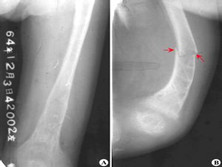

Fanconi综合征

范可尼综合征(Fanconisyndrome,又称deToni-Debre-Fa...

佝偻病、失明